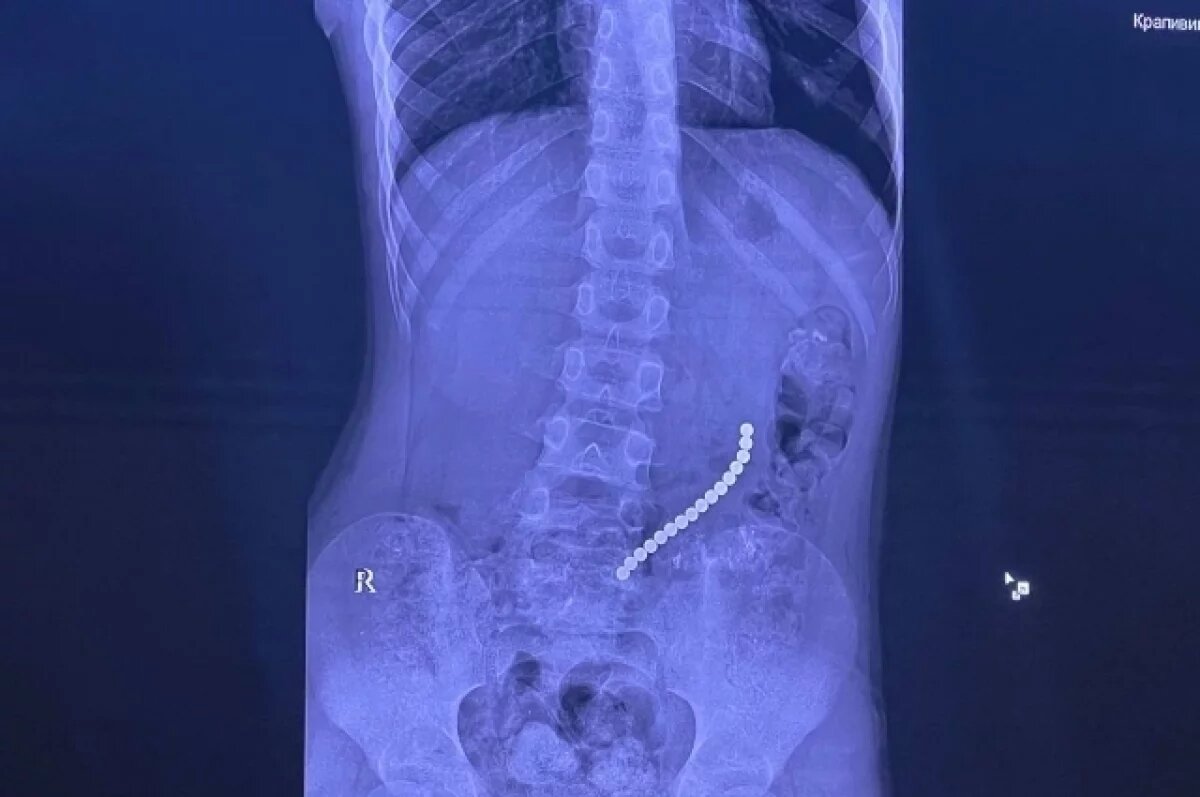

Случаи, когда иркутские врачи извлекают из желудочно-кишечного тракта детей инородные предметы, возникают достаточно часто. Но есть вещи, которые при проглатывании становятся наиболее опасными. Среди них – батарейки и магниты – особенно, когда их несколько. Об одном из таких случаев рассказал главный врач Иркутской областной клинической больницы Юрий Козлов. «8-летний мальчик поступил в клинику с «острым животом» - инородные тела вызвали повреждение желудочно-кишечного тракта. Несколько шариковых магнитов соединились между собой в различных сегментах внутренних органов, - рассказывает Юрий Козлов. – Очень редкое сочетание: одни магниты были в желудке, другие – в начальном отделе толстой кишки». Это привело к образованию фистулы: сообщения между желудком и кишкой. При помощи технологий минимально-инвазивной хирургии врачи разделили органы и восстановили их целостность после извлечения инородных тел.

«8-летний мальчик поступил в клинику с «острым животом» - инородные тела вызвали повреждение желудочно-кишечного тракта. Несколько шариковых магнитов соединились между собой в различных сегментах внутренних органов, - рассказывает Юрий Козлов. – Очень редкое сочетание: одни магниты были в желудке, другие – в начальном отделе толстой кишки».

Это привело к образованию фистулы: сообщения между желудком и кишкой. При помощи технологий минимально-инвазивной хирургии врачи разделили органы и восстановили их целостность после извлечения инородных тел.